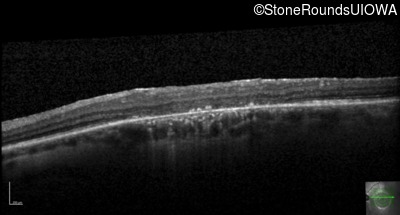

Optical Coherence Tomography - Left - 20/100 sc

Exemplar / OCT Stack